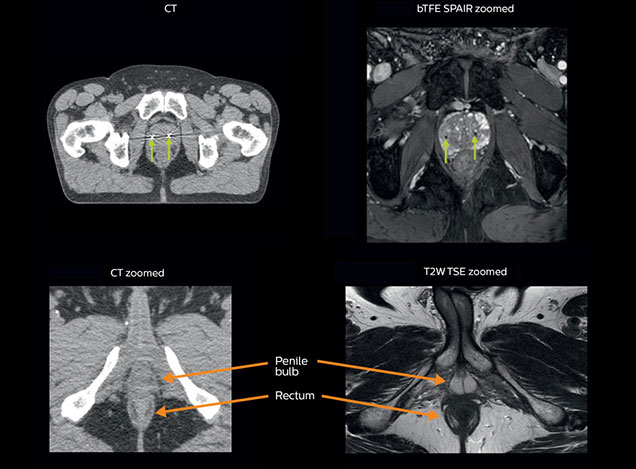

Visualizing critical structures with MRI before prostate radiation therapy

A 63-year-old patient with prostate cancer, cT3bNxM, Gleason 7, underwent MRI on Ingenia 3.0T MR-RT before radiation therapy.

Intraprostatic lesions are visible on the bTFE MR image, but not on the CT image. MRI shows excellent soft-tissue contrast for the visualization of critical structures like the rectum and penile bulb.

Fiducial markers (green arrows) are used in registration of MR images to CT, to transfer the MR-based delineations onto the CT image dataset.

MRI is capable of visualizing the prostate and the surrounding organs such as rectum, penile bulb, bladder, the apex and seminal vesicles, as well as visualizing intra-prostatic lesions [2,4].

“All our patients undergo an MRI exam – along with CT – before radiotherapy of the prostate,” says Dr. Philippens. “For prostate delineation, we are scanning a balanced TFE with fat suppression. We can also see the gold fiducial markers in these images, which are used for position verification and are therefore used for registration to CT. For geometric accuracy of the image, we choose a 3D sequence, which is corrected for the gradient non-linearities in all directions.

“In addition to helping in delineation of the prostate, MRI also helps in visualizing the lesions inside the prostate, which may not be possible in CT.

“When we can visualize intraprostatic lesions, the radiation therapist can then plan to boost them, giving a higher dose to those lesions instead of giving a uniform dose to the whole prostate, in the hope to better treat the patient and have less risk of recurrent tumors. However, this is not yet clinical routine. For visualizing the lesions, we not only use anatomical, T2-weighted imaging, but also diffusion weighted MRI and dynamic contrast- enhanced MRI."